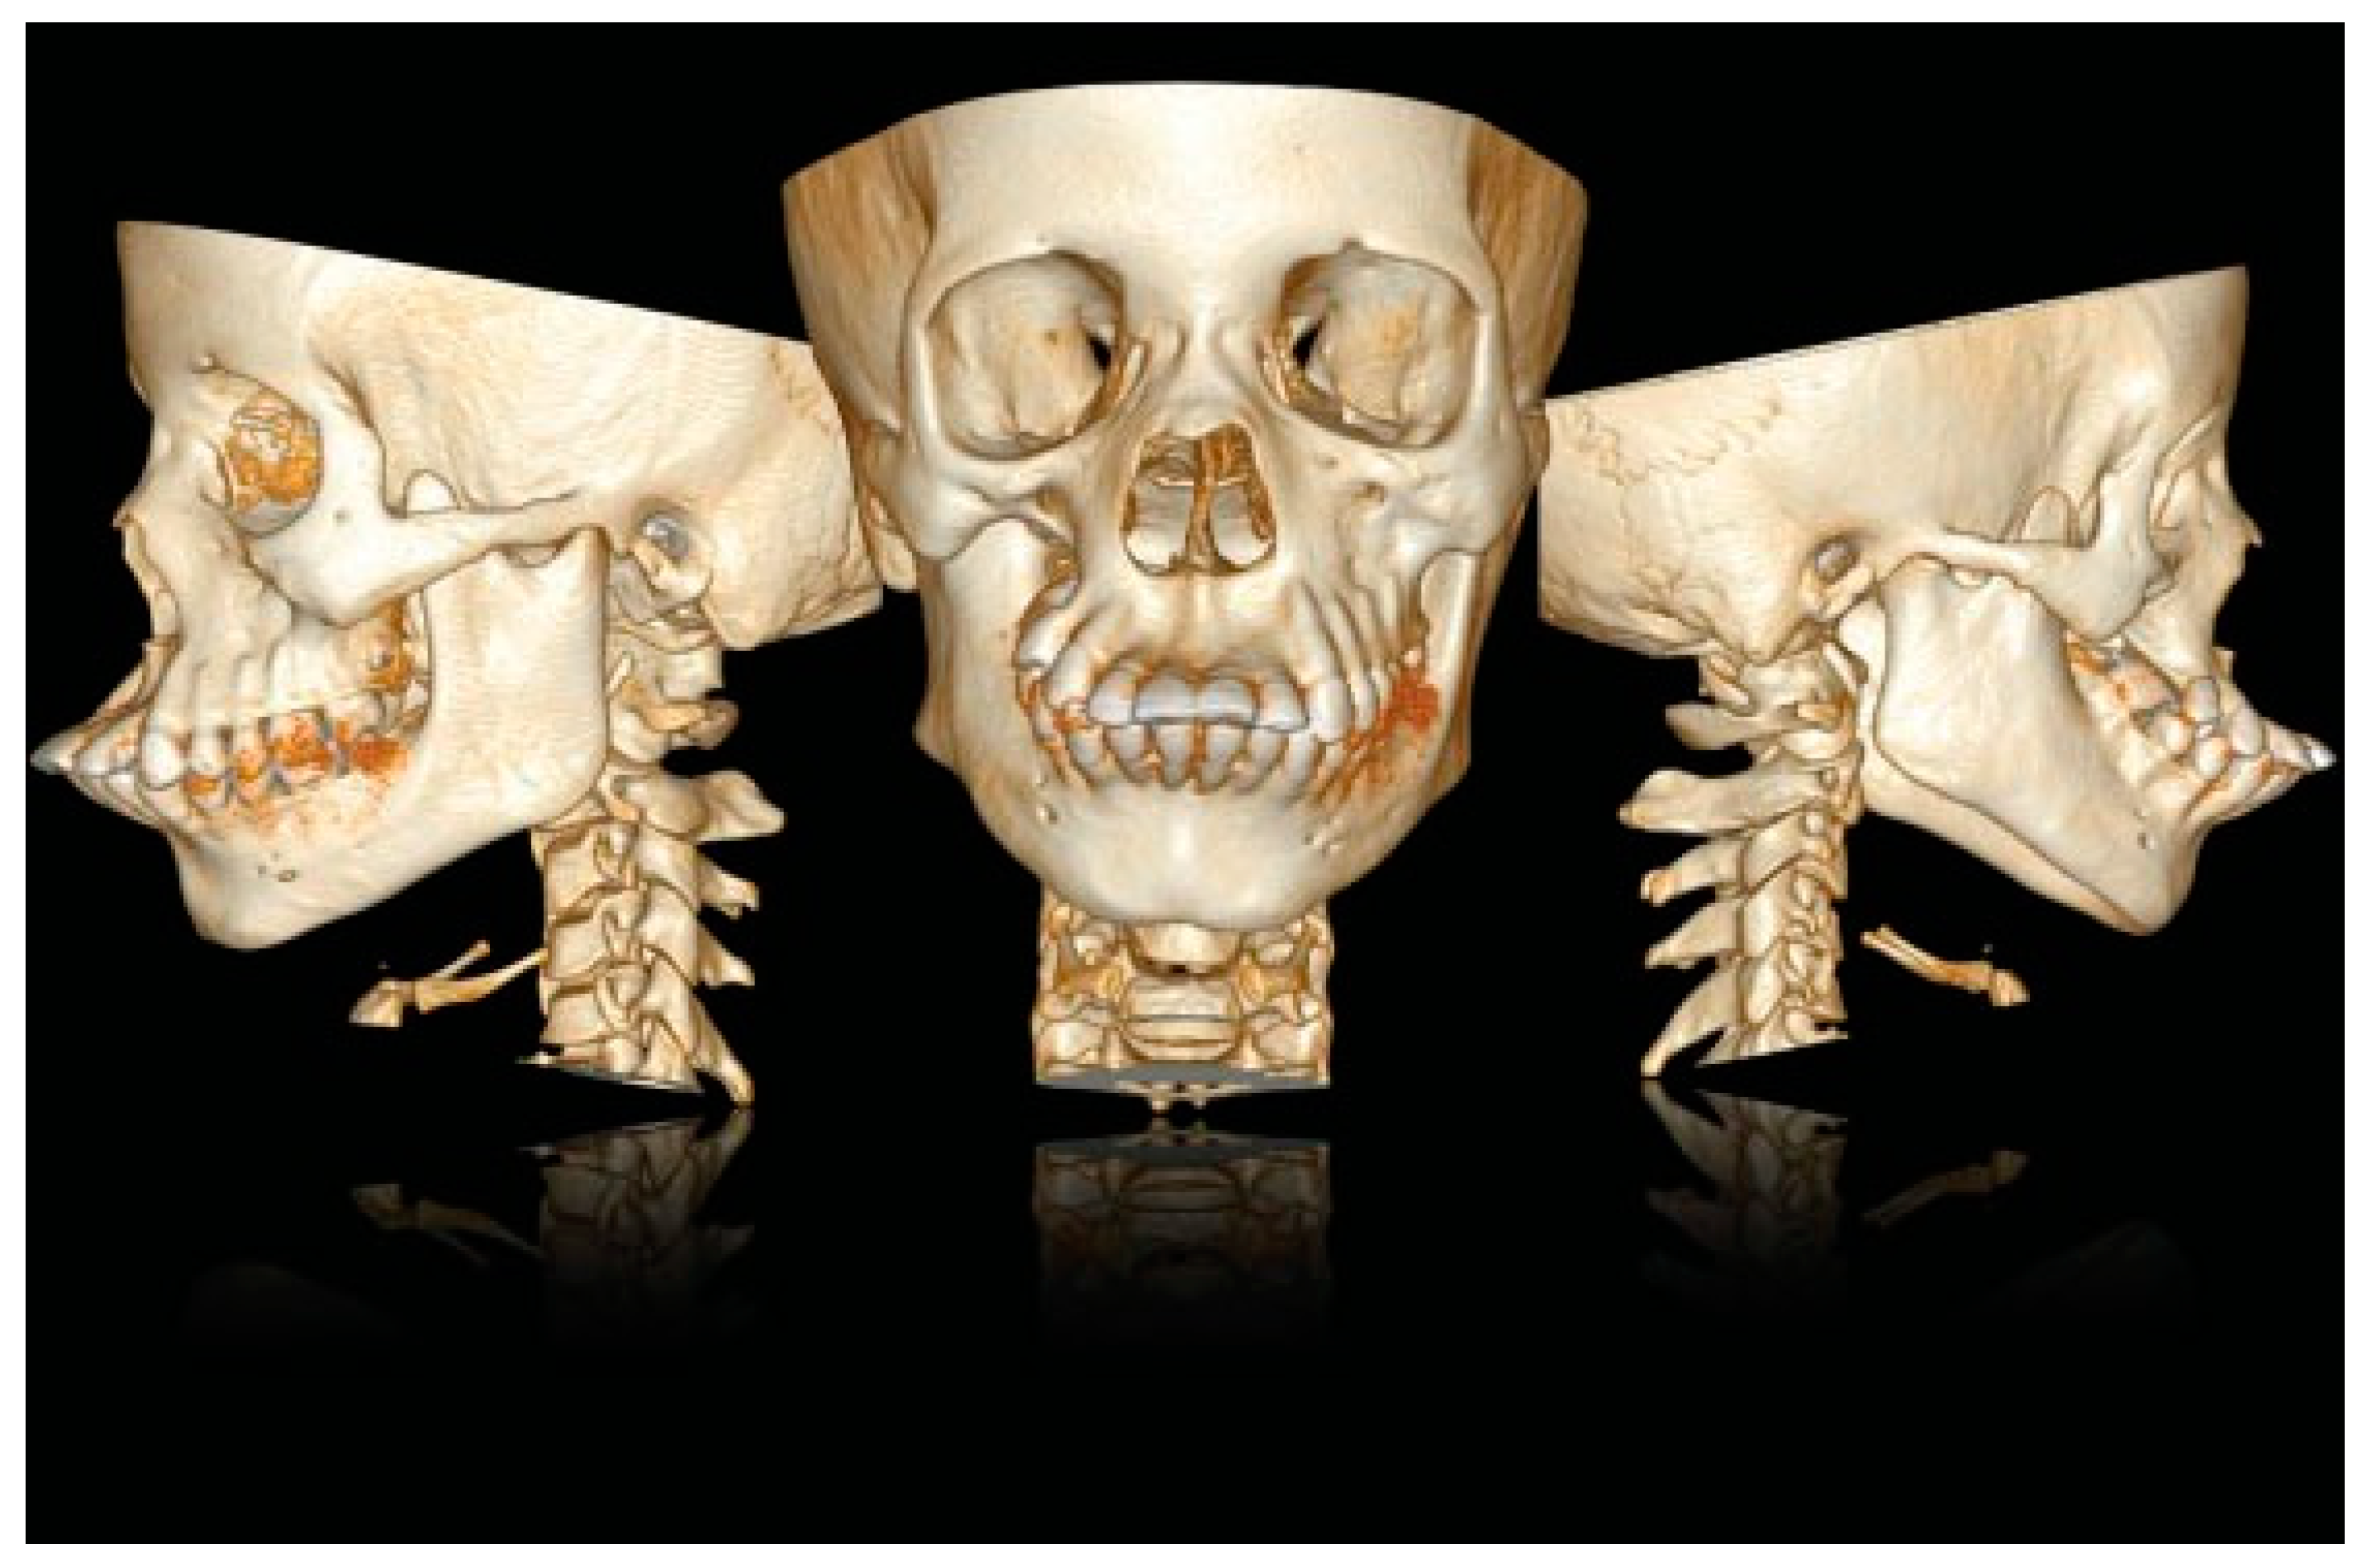

Figure 5. CT scan with 3D reconstruction: upper and lower jaw dental collapse with labioversion, dental agenesis, and right hemifacial microsomia.

A CT scan of the head with 3D reconstruction (Figure 1, Figure 2, Figure 3, Figure 4 and Figure 5) confirmed a maxillomandibular fusion associated with a cleft palate, agenesis of the right turbinate, and right hemifacial microsomia (Laster type 2b syngnathia). Both temporomandibular joints (TMJs) were normal and showed no bony ankylosis (fibrous ankylosis could not be excluded with the given data).

A facial angio-CT scan was performed to study cervical vascular anatomy and to discard anatomical variants at the level of the internal maxillary artery. Heteroanamnesis revealed a family history of endogamy and second-degree consanguinity. 3D planning of the surgery was performed with SimPlant O&O (Materialise Dental/Dentsply Implants, Mölndal, Sweden) to study the patient’s anatomy and design the necessary osteotomies to separate the jaws (Figure 6 and Figure 7). Thanks to the 3D preparation, the surgical access could be decided on an intraoral approach with sufficient exposure to do the osteotomy and ostectomy seemed feasible. In case the access was insufficient, a hemicoronal approach with osteotomy of the zygomatic arch had to be considered.